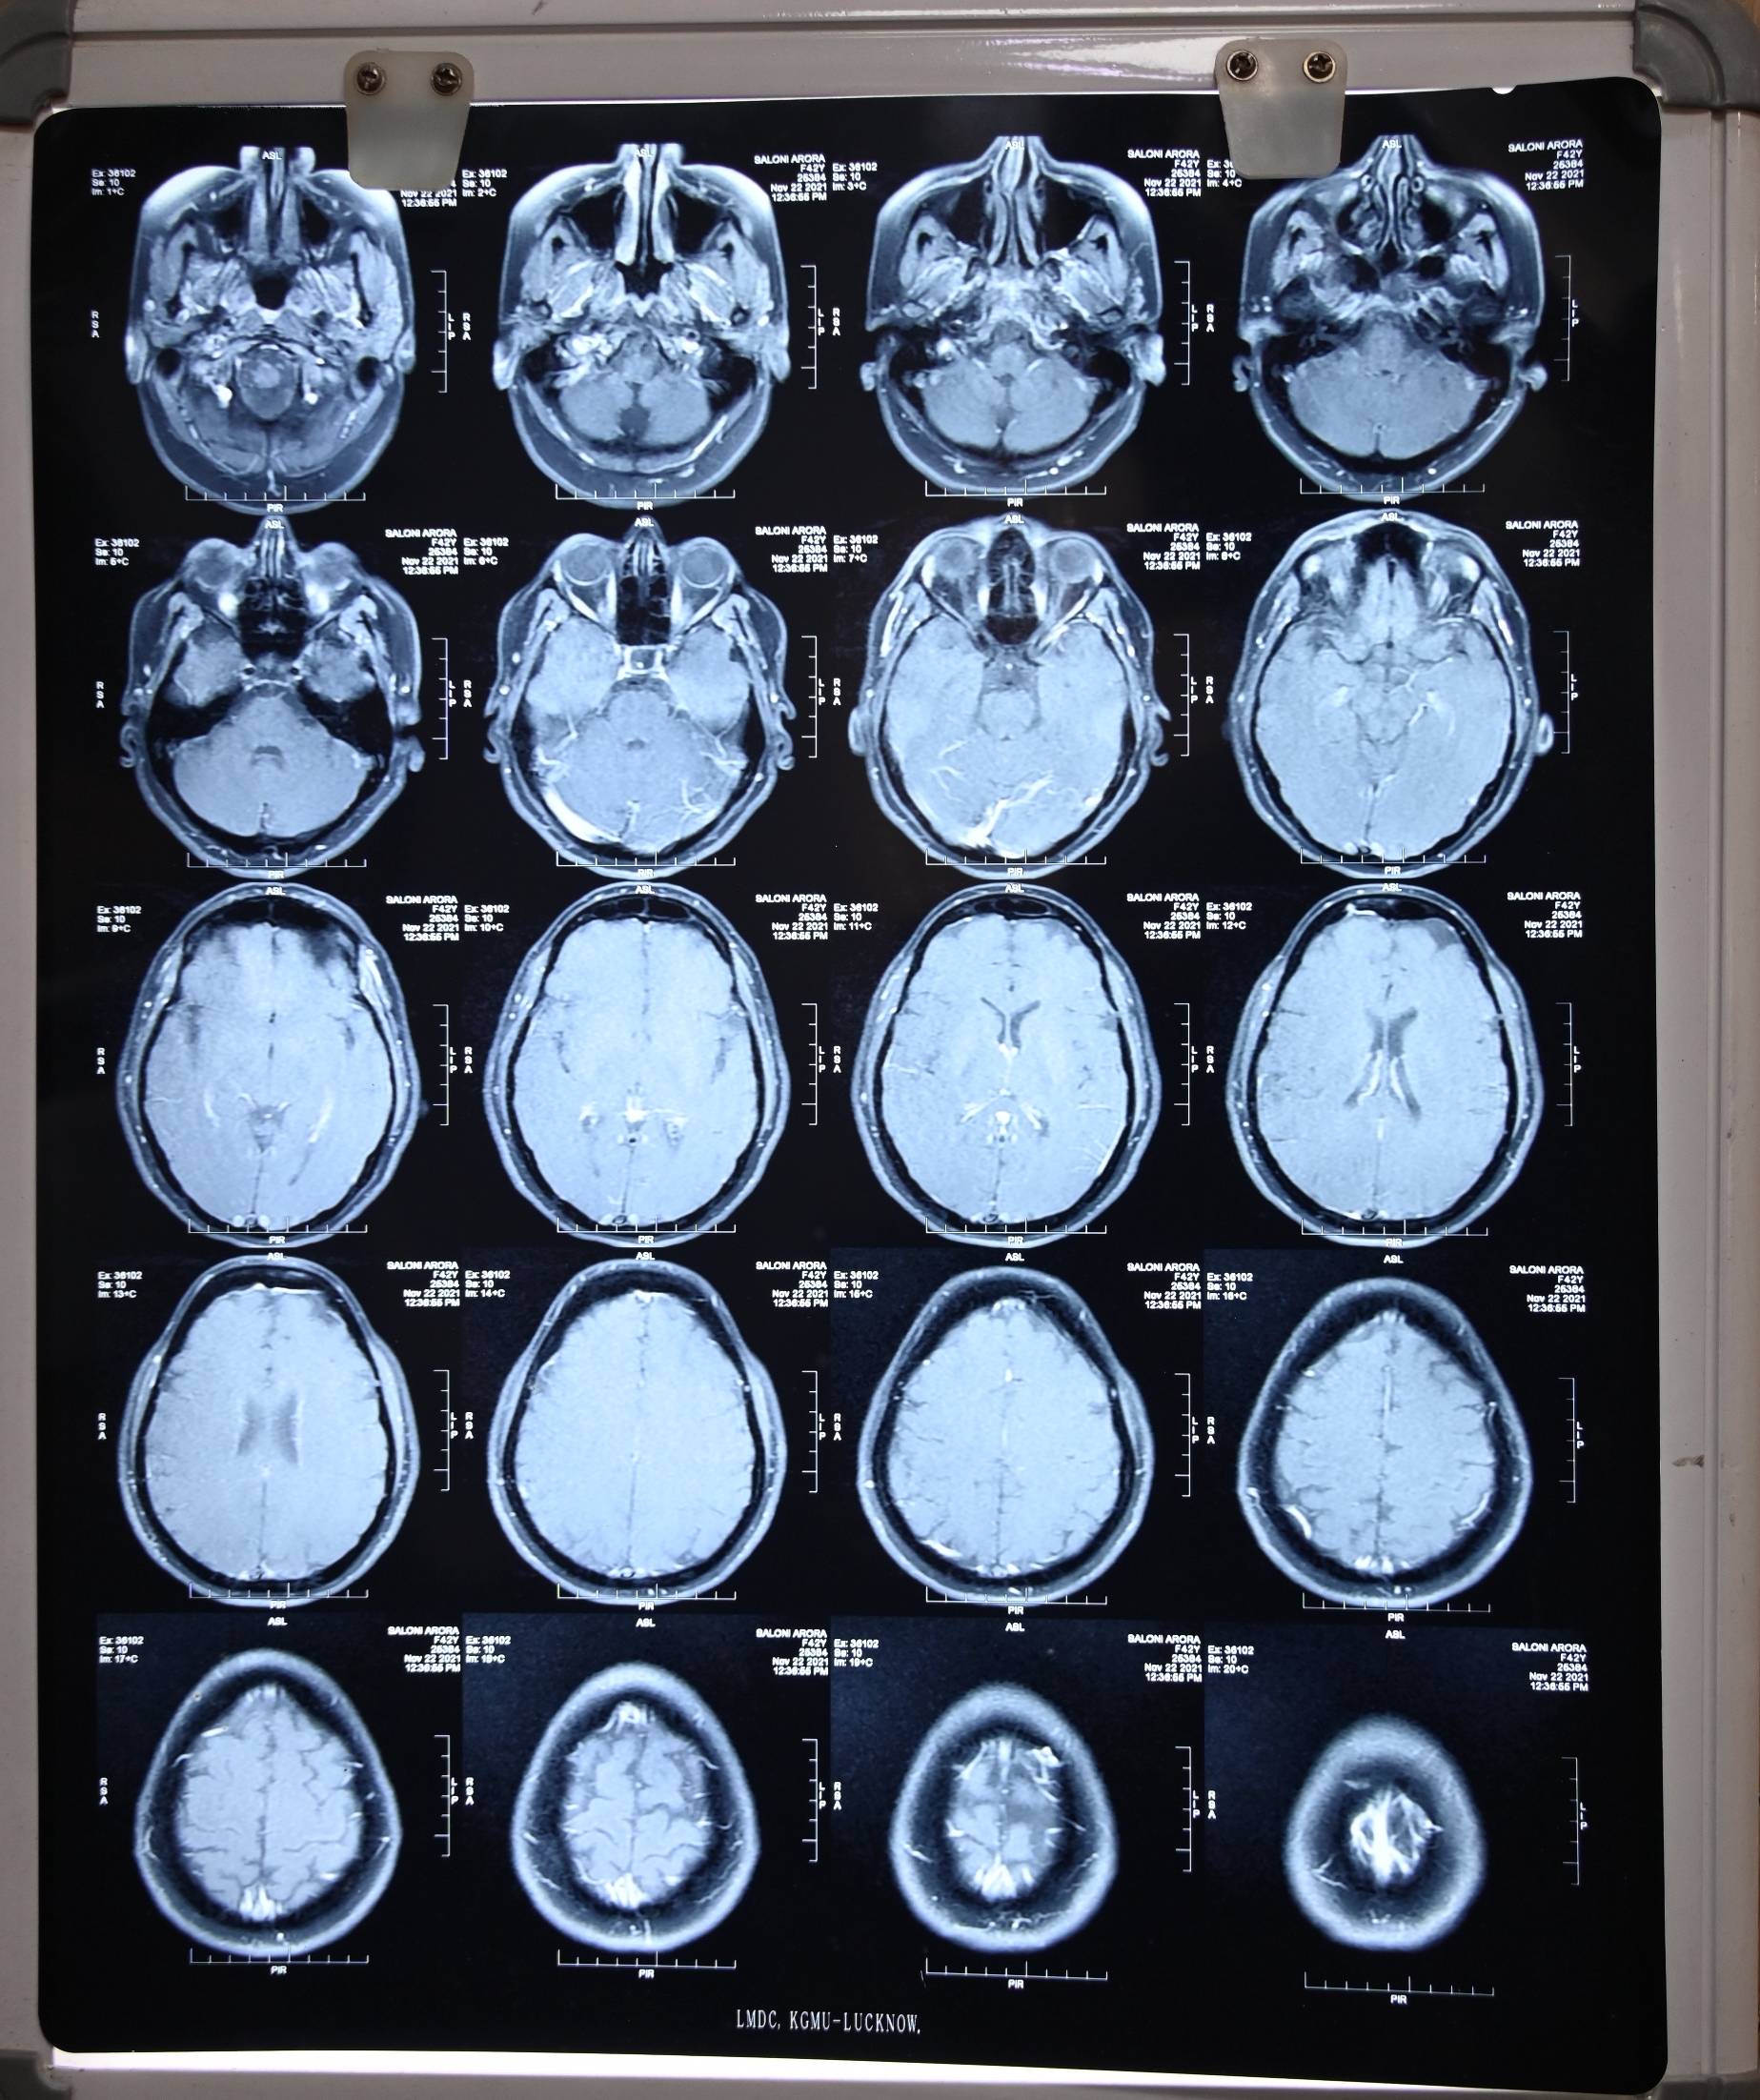

There is no Csf leak for many months. She got advised to undergo CT cisternography to rule out any remaining defect.

She awas again advised for the Ct cisternography but our of fear or anxiety she is postponing the investigation, which is crucial in determining the cure.

Dr Ravi talked with patient over the zoom call on 18th March 2024. She got cured for her CSF Rhinorrhea trouble. For last 10 months she never experienced any single drop of CSF leak. She got advised for its prognostic lab test CT cisternography, but she is constantly making some excuses for the same. Her migraine trouble also got cured.